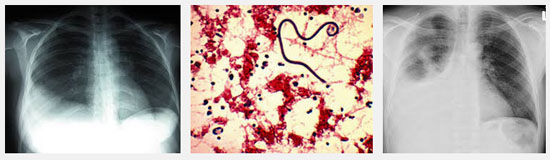

CTMTP: Bạch cầu tăng 13.000/mm3, bạch cầu ái toan chiếm ưu thế 11%, bạch cầu đa nhân trung tính 70%; chỉ số CRP: 47 mg/L (bình thường < 3); men gan AST: 88 U/L, ALT: 100 U/L, GGT: 100 U/L; men tim CK-MB, Troponin T: Âm tính; X-quang phôi: bóng tim lớn nhẹ, tràn dịch màng phổi phía bên (T); siêu âm tim: màng ngoài tim Echo kém, dày 3 - 5 mm; siêu âm bụng: Gan lách bình thường, ghi nhận TDMP (T), bề dày lớp dịch 37 mm.

Sau 3 ngày điều trị bệnh nhân vẫn còn sốt, đau ngực tăng, đau cả ngực (P) và (T). X-quang phổi kiểm tra cho thấy TDMP bên (T) tăng. Siêu âm màng phôi cho hình ảnh TDMP 2 bên. Bệnh nhân được chọc dịch màng phổi để xét nghiệm, kết quả như sau:

-X-quang phổi, siêu âm không còn dịch màng phổi.

Ngày 01/7/2014 | Ngày 08/7/2014 | Ngày 25/7/2014 |